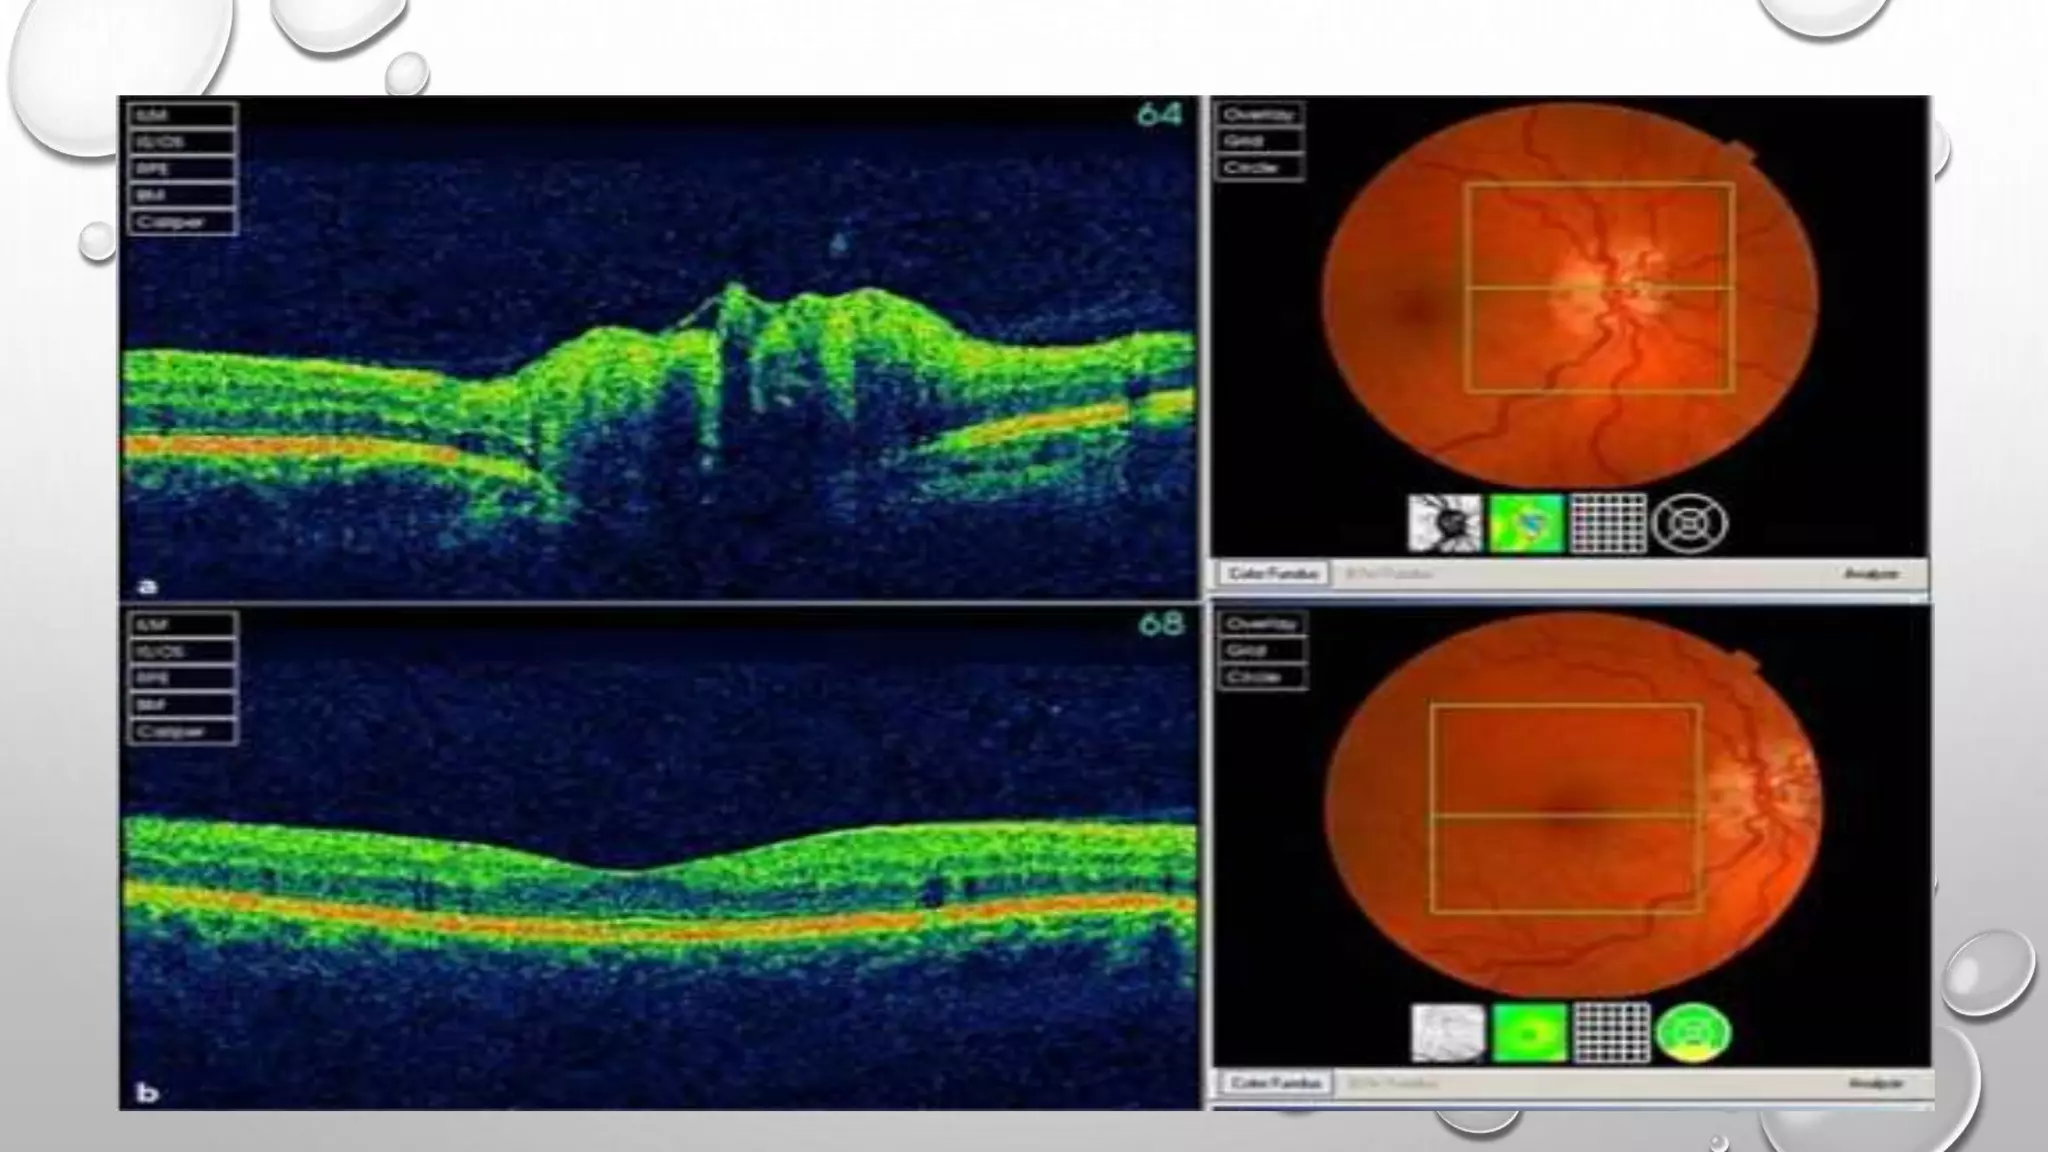

Ganglion cell–inner plexiform layer and MS:

(GCIPL) thickness correlates better with visual function and radiologic markers of MS

disease activity, compared to RNFL thinning and that due to:

GCIPL thickness is unaffected by inflammatory edema in the acute stages of acute

MSON

GCIPL atrophy occurs rapidly following acute MSON (even in a matter of days) and

is marked at 1 month following the ictus.

GCIPL atrophy precedes macular volume and macular RNFL loss.

GANGLION CELL–INNER PLEXIFORM LAYER AND MS “CONT.”

Indeed, GCIPL loss in the first month following acute MSON is a good

predictor of short-term visual dysfunction; if the loss does not exceed 7

μm, acuity recovery; good visual field and color vision recovery will

usually take place.